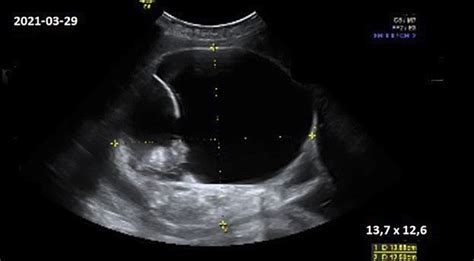

Šiuo metu vaisius "pasirenka" padėtį, kuria ir gims. Gydytojas ar akušerė, o kartais ir pati nėščioji, gali nustatyti šią padėtį. Esant neaiškumams, atliekamas ultragarsinis tyrimas.

Nėštumas - jautrus metas, kai moterys nerimauja dėl vaiko sveikatos. Rekomenduojamos ultragarsinės patikros padeda laiku nustatyti galimus vystymosi sutrikimus. Šiuolaikinė medicina turi galimybes gydyti ir operuoti vaisių motinos gimdoje.